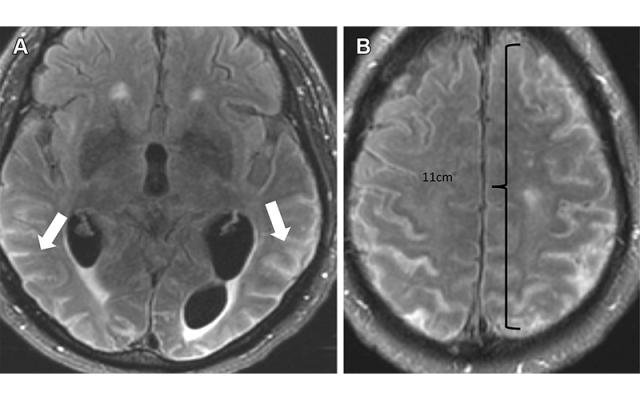

一名因AD接受阿杜卡努单抗治疗的头痛恶化的76岁男性发生重度ARIA-E(积液)。2021年12月(足量给药后3周)的轴位颅脑MR图像显示沿脑沟有多灶性渗出,FLAIR高信号(A箭头),超过10 cm(重度),软脑膜轻度强化(B)。暂停治疗,停止治疗后观察到积液完全消退ARIA 患者有时会出现头痛,但通常无症状,只有通过 MRI 才能诊断。

ARIA-E 是单克隆抗体治疗最常见的副作用。在两个III期临床试验(EMERGE and ENGAGE)中, 使用批准剂量的患者中有 35% 患有 ARIA-E。这些试验还表明,大多数 ARIA-E 病例无临床症状,98% 在影像学随访中得到解决。ARIA-E 最常发生在治疗的 3 到 6 个月之间,在前 9 个月后发病率急剧下降。ARIA-H 通常出现在用单克隆抗体治疗的约 15-20% 的患者中。与 ARIA-E 不同,ARIA-H 不是短暂的,不会随着时间的推移而消失。